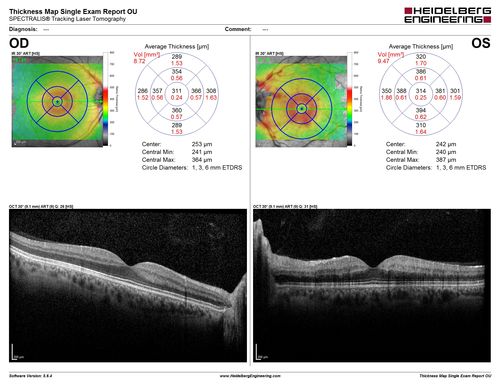

Central retinal artery and vein occlusion - Protein C Deficiency 33 year old male

33 year old male with vision loss for 3 hours.  VA 20/12 right eye, 5/200 left eye.  He has a protein C deficiency.  The left eye recovered vision in about 1 month to 20/16.  FA shows very slow recirculation time.